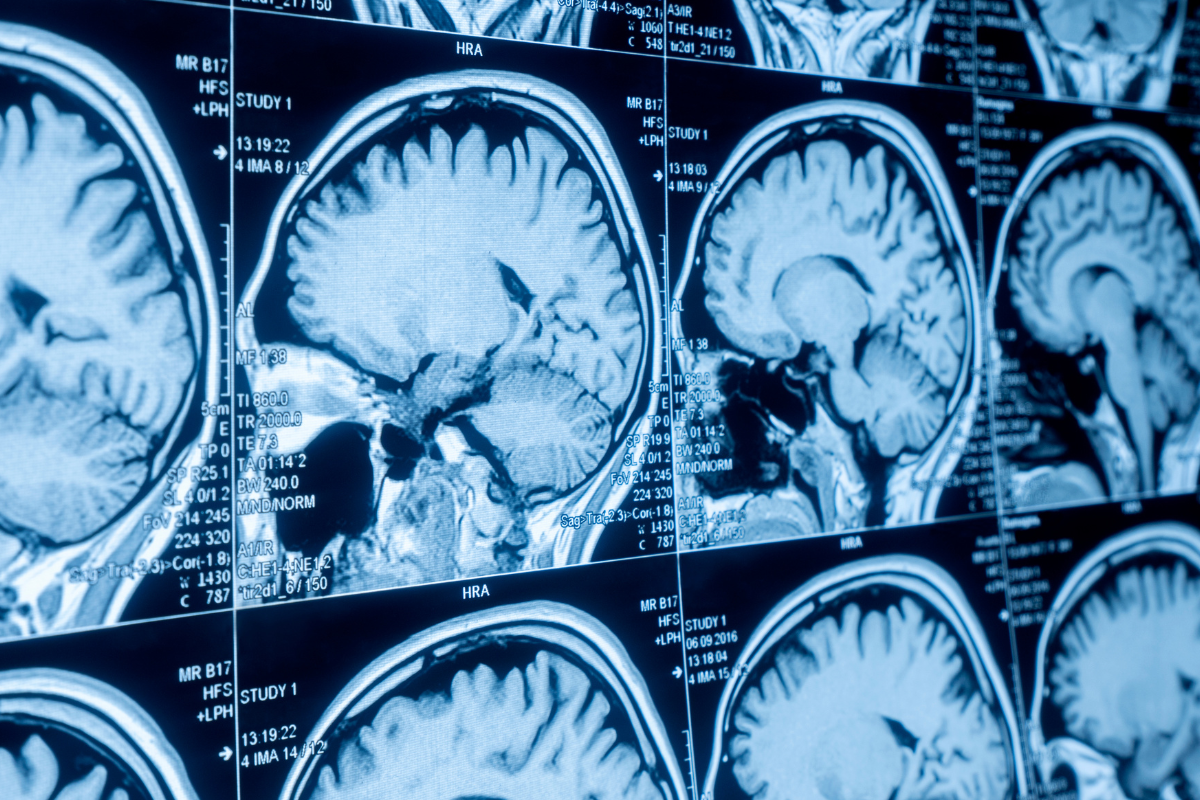

What makes these findings so remarkable is that the ‘old brain’ in this study wasn’t measured by memory tests or MRI scans. It was detected purely through protein signals in the blood. These signals weren’t just correlated with ageing; they were predictive. And ultimately, while a fast-ageing brain could indicate cognitive decline, it could also show a higher risk of dying earlier.